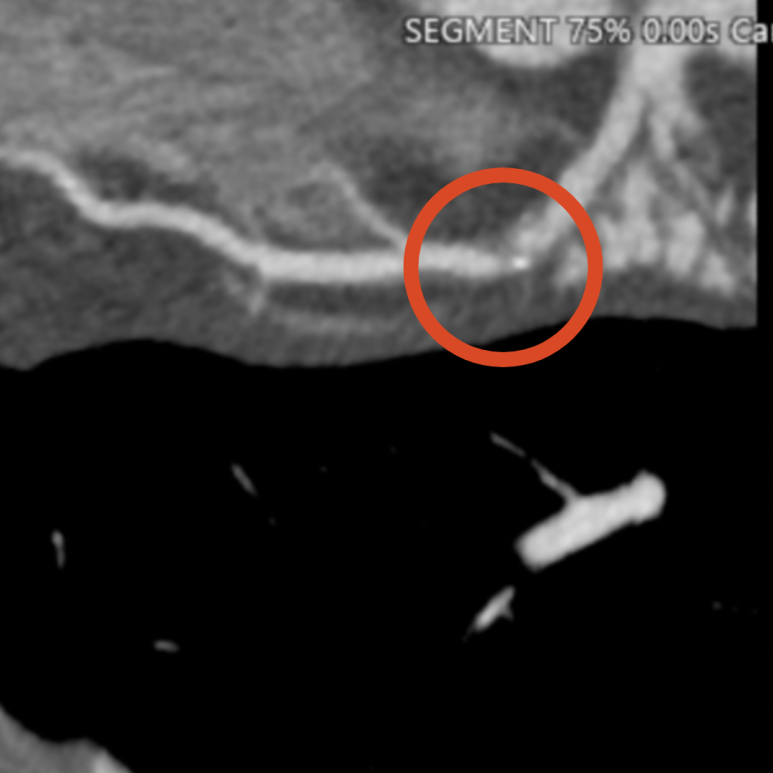

ECG·심초음파 특이 소견 없음. 관상동맥 CT 검사 결과 좌관상동맥 2부위 중증 협착 명확히 확인되었고, 즉시 스텐트 치료 필요성 높아 상급병원으로 전원.

• 3D 관상동맥: 협착 부위 3D 관상동맥: 협착 부위

• 좌측 관상동맥 2곳에서 협착 발견 좌측 관상동맥 2곳에서 협착 발견